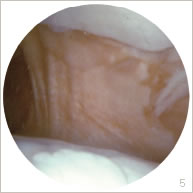

La rétraction de l’aileron externe peut provoquer un dysfonctionnement rotulien sous la forme d’une bascule isolée occasionnant des phénomènes d’hyperpressions cartilagineuses ou associé à un véritable déplacement de celle-ci sur le côté responsable d’un défaut de contact des surfaces articulaires (figures 2 et 6). Ceci peut occasionner une gêne à type de douleurs, de blocages, de gonflements, ou d’instabilité.